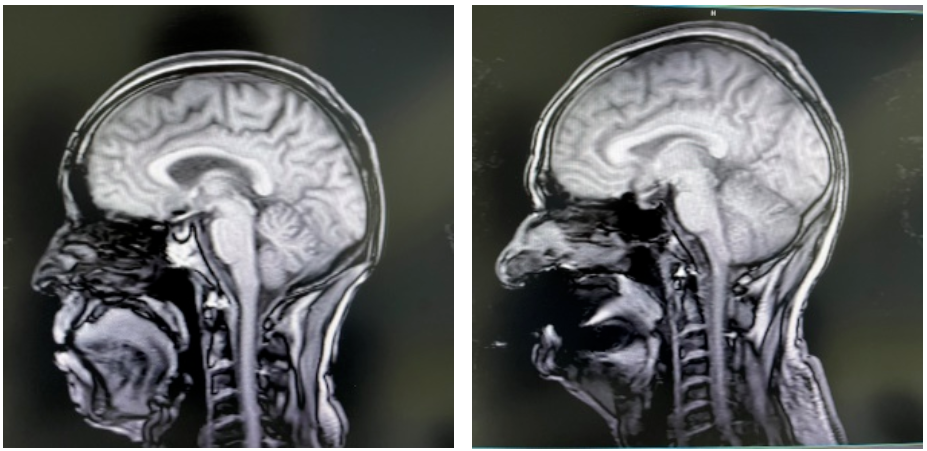

左:头部失状扫描图;右:假牙干扰后的伪影